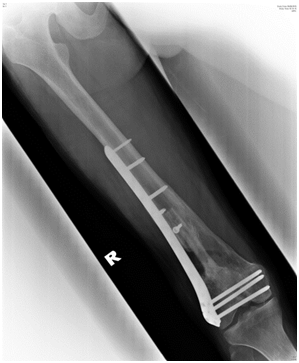

The purpose of this case report is to demonstrate that despite the severity of the injury, good union and functional outcome is achievable using the relatively simple technique of distal femur plating with locking plate augmented with autogenous non-vascularized fibula bone graft.We presented a case of a 20-year-old man who had an alleged motor vehicle accident. He presented to the emergency department with pain and bleeding of the right thigh. On examination, Glasgow Coma Scale score was 15 of 15. There was a deep laceration wound at the anterolateral aspect of his distal right thigh measuring 8cm by 4cm. There was deformity, local tenderness, and abnormal mobility in the distal part of the thigh but no distal neurovascular deficit. Radiographs of the right femur revealed a severely comminuted supracondylar fracture with bone loss and intraarticular involvement (Figure 1A & 1B). The fracture was classified as AO type 33-C3.

Postoperative radiograph showed acceptable fracture alignment with autogenous fibular graft inside the medullary canal (Figures 2A & 2B).